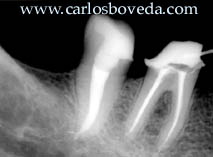

El

paciente M.E. nos es referido para

evaluación endodóntica

pre-protésica del maxilar inferior

lado derecho. La imagen a la izquierda es

una radiovisiografía y la derecha

es una radiografía convencional

digitalizada del área en el momento

que se presenta esta segunda

discusión en el mismo paciente. Su

protesista nos consultó en

relación a la condición

endodóntica de la zona,

particularmente por el segundo molar,

donde se decidió rehacer un

tratamiento endodóntico que

presenta una gran sobreextensión de

puntas de plata. En este momento la

discusión se centra en el tercer

molar.